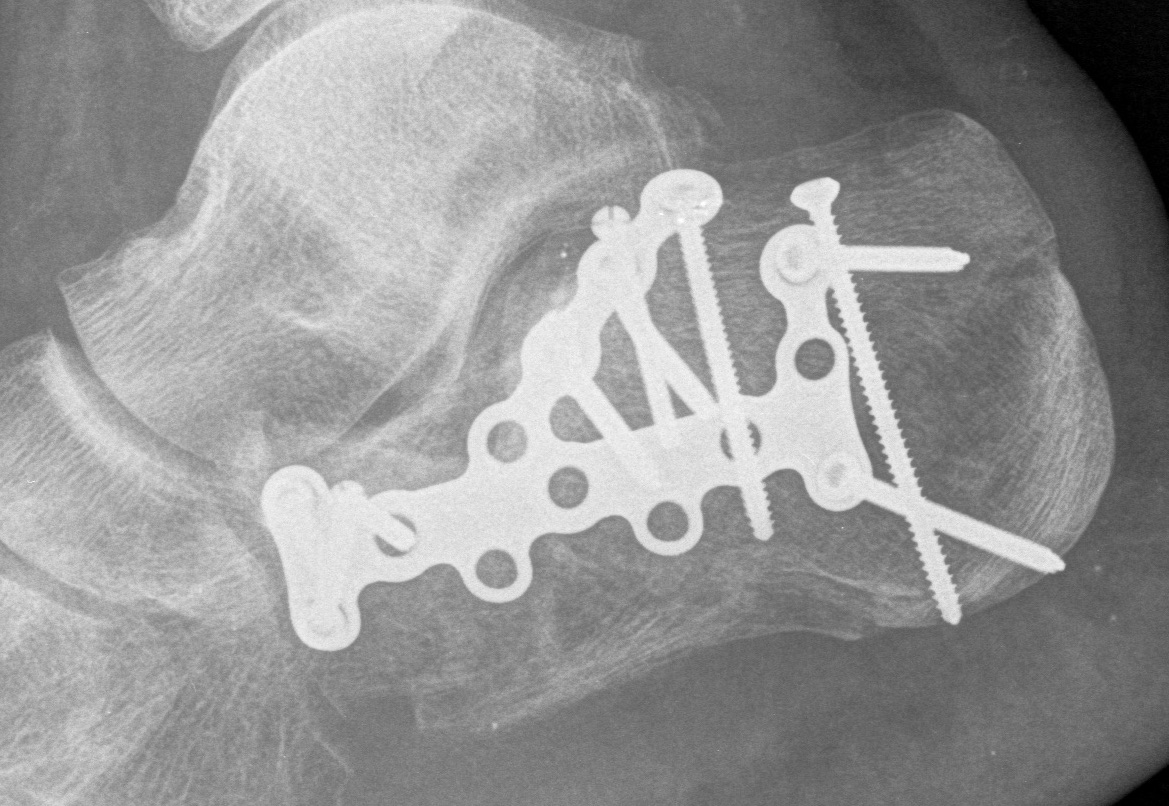

ORIF lateral plate using extensile lateral approach

Technique

AO surgery reference extensile lateral approach

AO surgery calcaneal ORIF lateral plate

Extensile lateral approach

- vertical limb: between tendoachilles and fibula

- horizontal limb: in line with 5th metatarsal towards CC joint

- full thickness flaps - care ++++ with apex of incision

- divide peroneal retinaculum

- peroneal tendons elevated

K wires to retract skin flap

- 2 in talus / 1 in fibula

Expose subtalar joint

Reduction of varus

- Steinmann pin into tuberosity

- can elevate and pull out of varus

Reduction of subtalar joint

- open lateral wall fragment to access to subtalar joint

- lamina spreader

- reduce and ORIF with screws

- reduce and ORIF sustentaculum fragment

Anatomical contoured locking plate